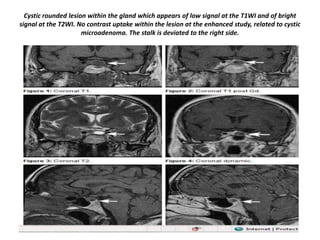

Cystic rounded lesion within the gland which appears of low signal at the T1WI and of bright

signal at the T2WI. No contrast uptake within the lesion at the enhanced study, related to cystic

microadenoma. The stalk is deviated to the right side.